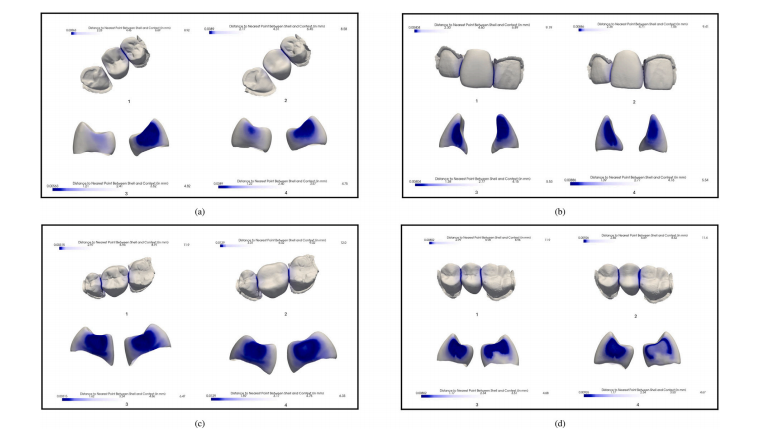

Fig. 8. Heatmap visualizations of the intersection function, displaying multiple cases for different tooth positions: (𝑎) position 24, (𝑏) position 11, (𝑐) position 16, and (𝑑) positionIn each case, subfigures (1) and (2) represent the ground truth and predicted distances, respectively, for both the crown and its context (neighboring teeth), with higher valueson the right side due to distances calculated from context points. Subfigure (3) represents the ground truth and subfigure (4) the prediction, showing only the crown withoutcontext, resulting in lower right-side values as these distances are measured solely between the crown and its nearest context points.

图8:交集函数的热图可视化,展示了不同牙齿位置的多个案例:(a) 位置24,(b) 位置11,(c) 位置16,以及 (d) 位置25。在每个案例中,子图(1)和(2)分别表示牙冠及其周围环境(相邻牙齿)的真实距离和预测距离,由于是根据周围环境点计算的距离,所以右侧的值较高。子图(3)表示真实情况,子图(4)表示预测情况,仅展示了牙冠而不包含周围环境,因此右侧的值较低,因为这些距离仅在牙冠与其最近的周围环境点之间测量。